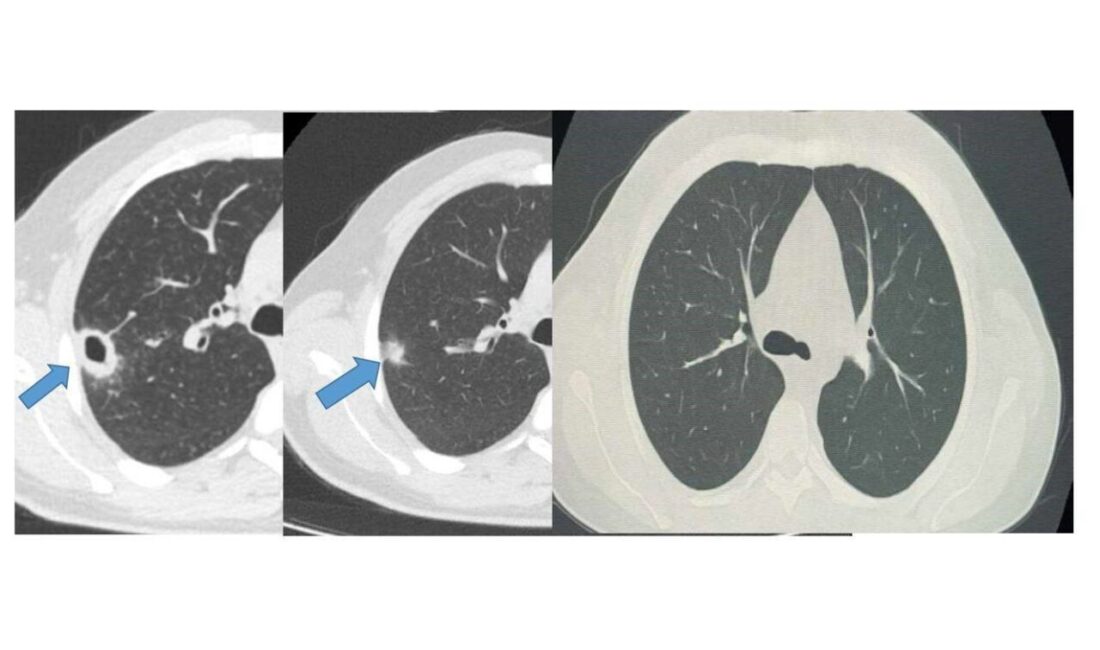

Bayburt Devlet Hastanesi’ne öksürük ve balgam problemiyke başvuran 50 yaşındaki bir hasta, yapılan muayene neticesinde akciğerinde kitle benzeri bir doku ile karşılaştı. Ancak, yapılan çeşitli tetkiklerde hastanın durumunun ciddi bir hastalık taşımadığı ortaya kondu. Erken teşhis ve uygun tedavi yöntemleri sayesinde hasta sağlığına kavuştu.

Göğüs hastalıkları alanında uzman Uzm. Dr. Hilal Sayma tarafından muayene edilen hastaya ileri düzey tetkikler için bronkoskopi uygulandı. Bu işlemin ardından elde edilen bulgular, lezyonun kanser ya da tüberküloz gibi ciddi bir hastalıkla ilişkisinin bulunmadığını gösterdi. Bu tespit, hasta için gerekli tedavin sürecinin başlatılmasını sağladı.

İki haftalık tedavi süresinin ardından yapılan kontrollerde hastanın akciğerindeki lezyonun büyük ölçüde gerilediği belirtildi. Sağlıklı bir duruma ulaşan hasta, başarıyla taburcu edildi ve genel durumunun iyi olduğu kaydedildi. Erken tanı ile gerçekleştirilen bu müdahale, ciddi sağlık sorunlarını önlemekte önemli bir rol oynadı.